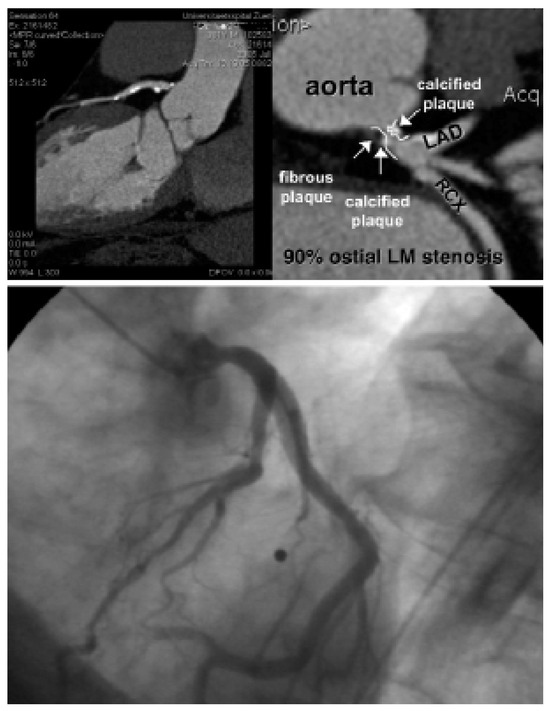

Biventricular pacing is an accepted therapy in patients suffering from terminal heart failure. Main obstacle however is the positioning of the left ventricular electrode via coronary sinus as well as its reliable fixation. This article describes in a...